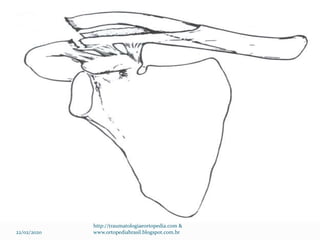

Padrões incomuns de fratura

 Separação fisária medial

 Normalmente necessário TC

 Maioria tem indicação de tto conservador

 Cirurgia: Lesão vascular ou laríngea aguda por desvio

posterior

 Fraturas da manga periosteal (pseudo LAC)

 Ombro Flutuante

“Fratura simultânea da clavícula e do colo glenoidal”

 Tratamento controverso